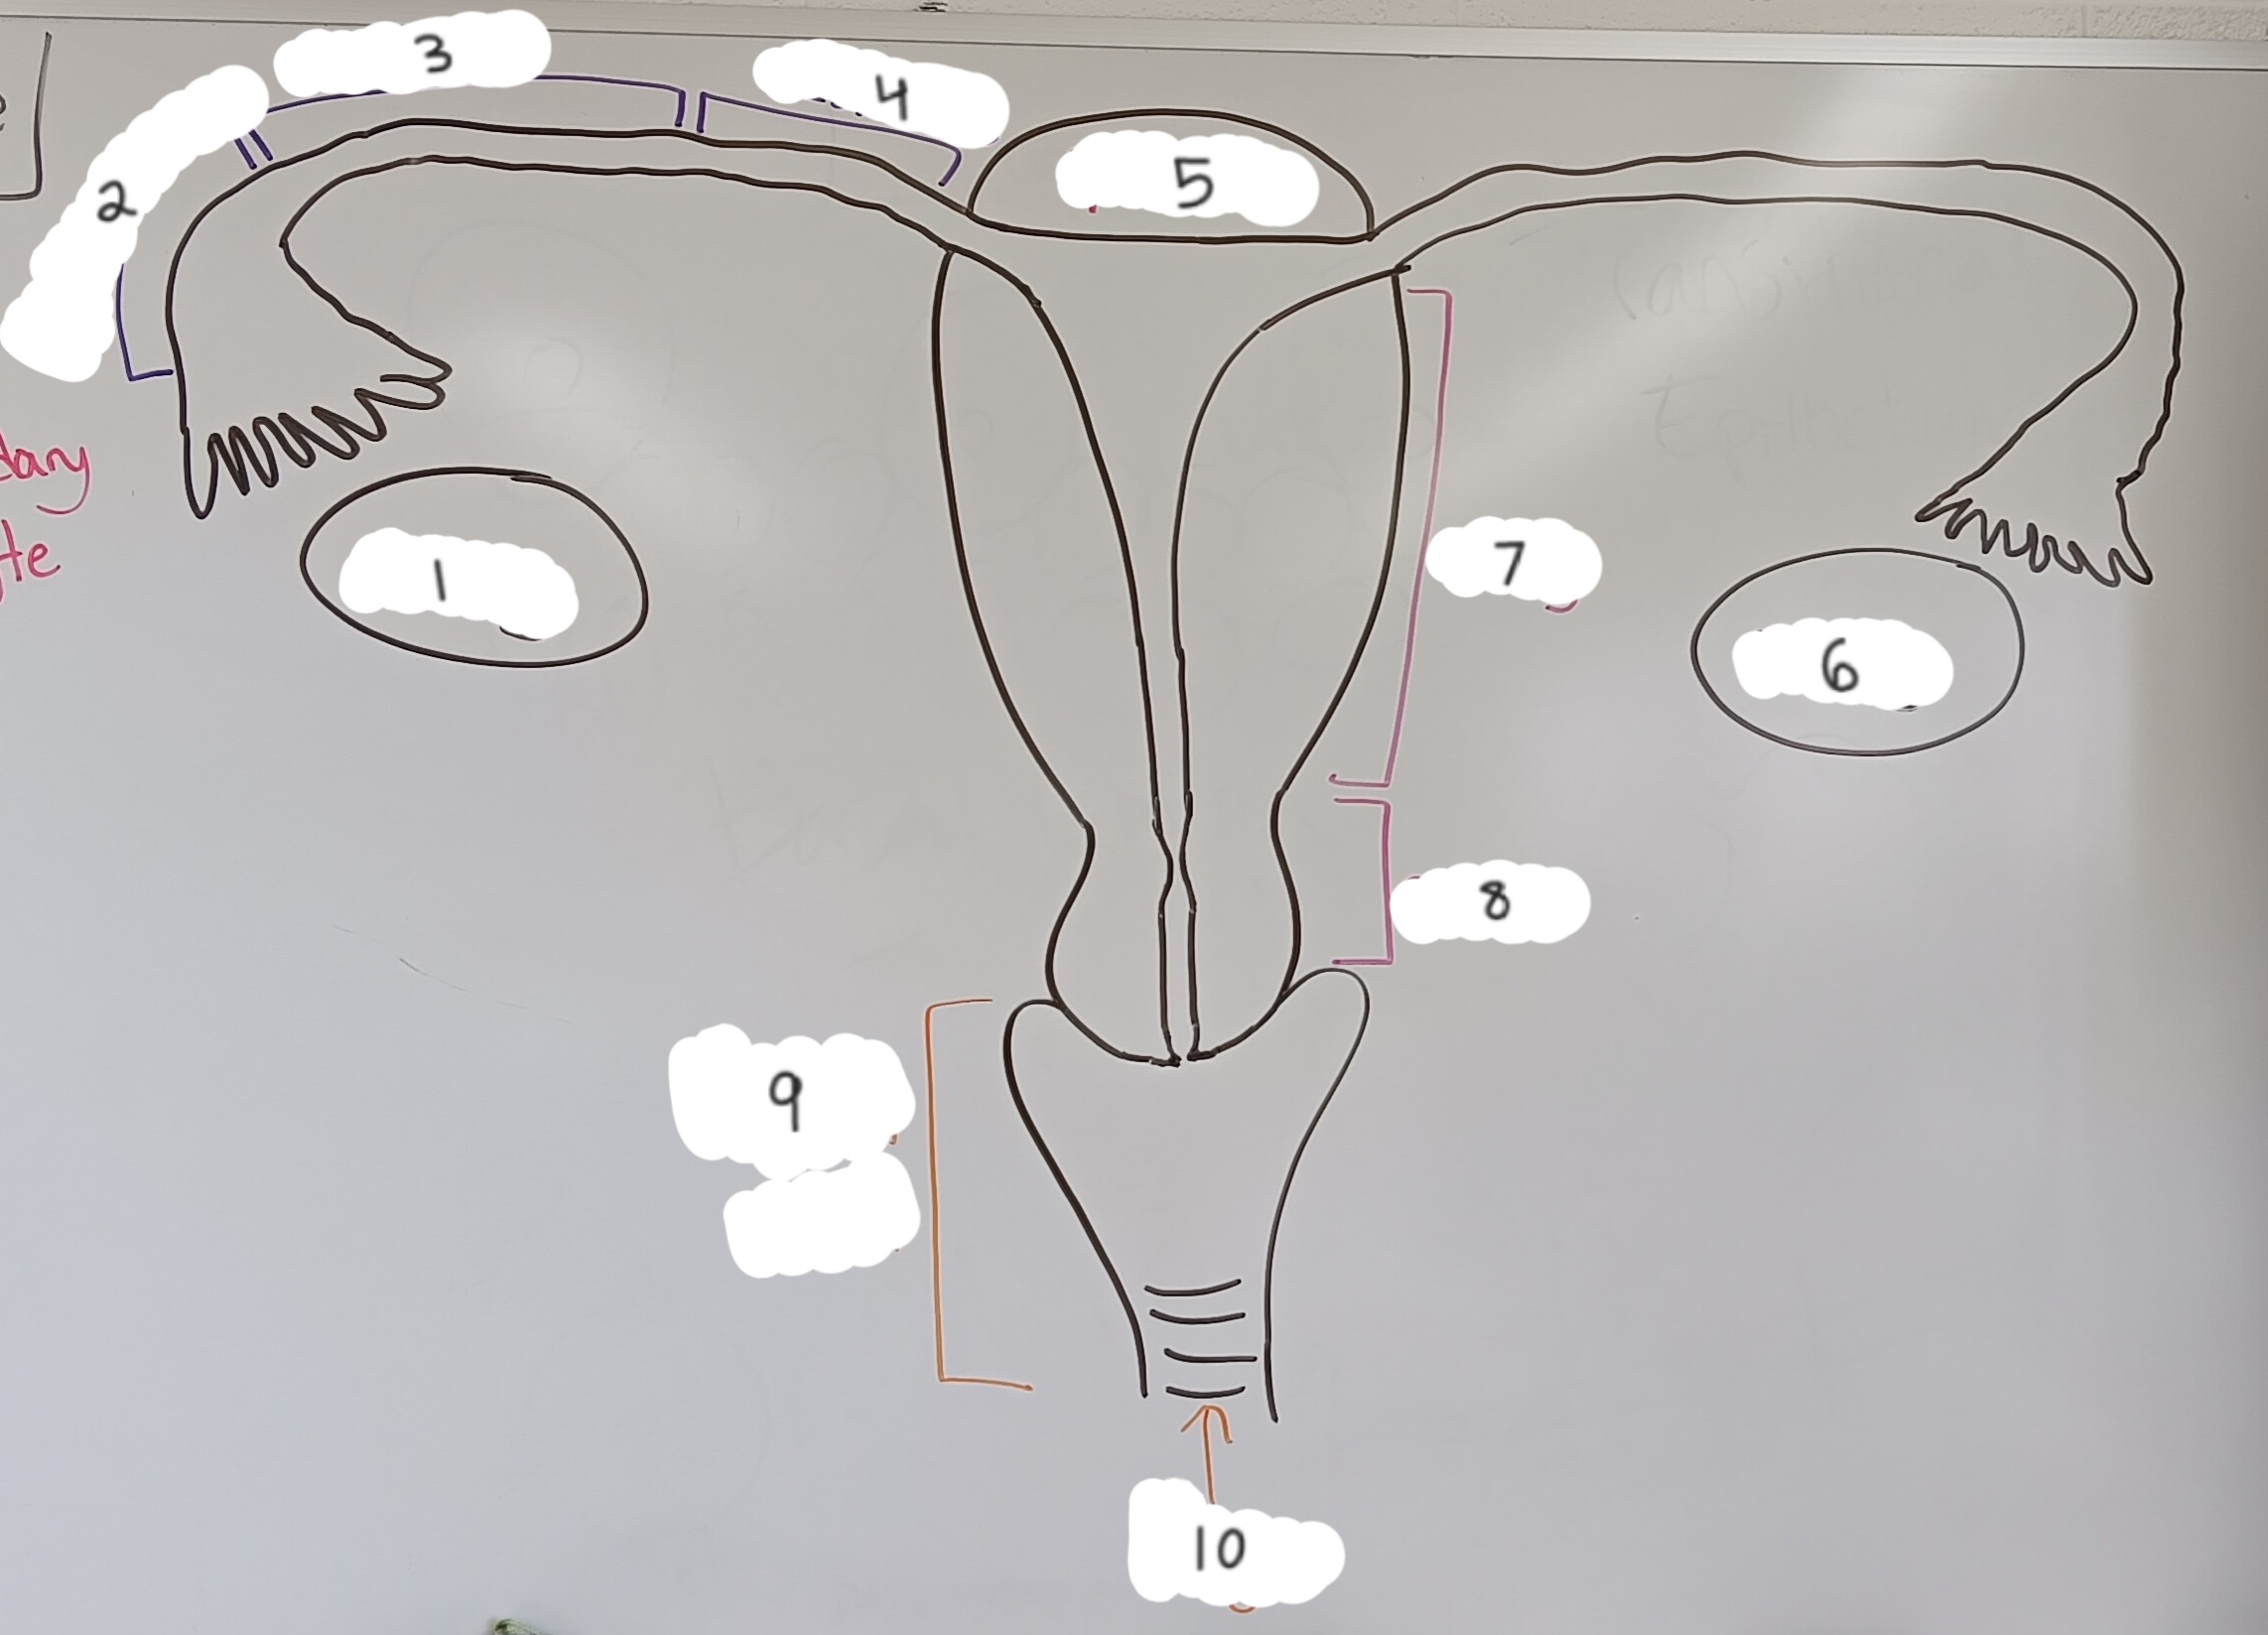

right ovary

1 (lt or rt)

infundibulum

2

ampulla

3

isthmus

4

fundus

5